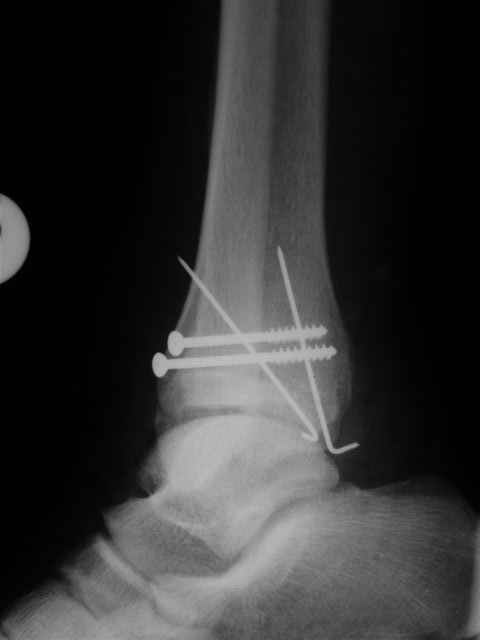

В первом письме я упомянул о закрытом повреждении правого голеностопного сустава, эверсионно-пронационный механизм травмы - перелом внутренней лодыжки( поперечный, на уровне суставной щели) и отрывной перелом бугорка Chaput. После обработки открытых переломов бедра и большеберцовой кости в эту же сессию перелом внутренней лодыжки фиксировал двумя расходящимися спицами, бугорок Chaput двумя тягловыми винтами 3,5 мм. Раны заживают благополучно. Учитывая повреждение наружной группы мышц, активное разгибание в голеностопном суставе ограничено. Пассивная + пассивно-активная мобилизация голеностопного сустава с физиотерапевтом.

Я предупреждал, что ничего сверхъестественного. Каюсь, что одна из спиц прошла несколько дальше, чем нужно было, но главное - перелом стабилизирован и больной работает суставом в полном объёме, несмотря на представленную раннее травму коленного сустава.